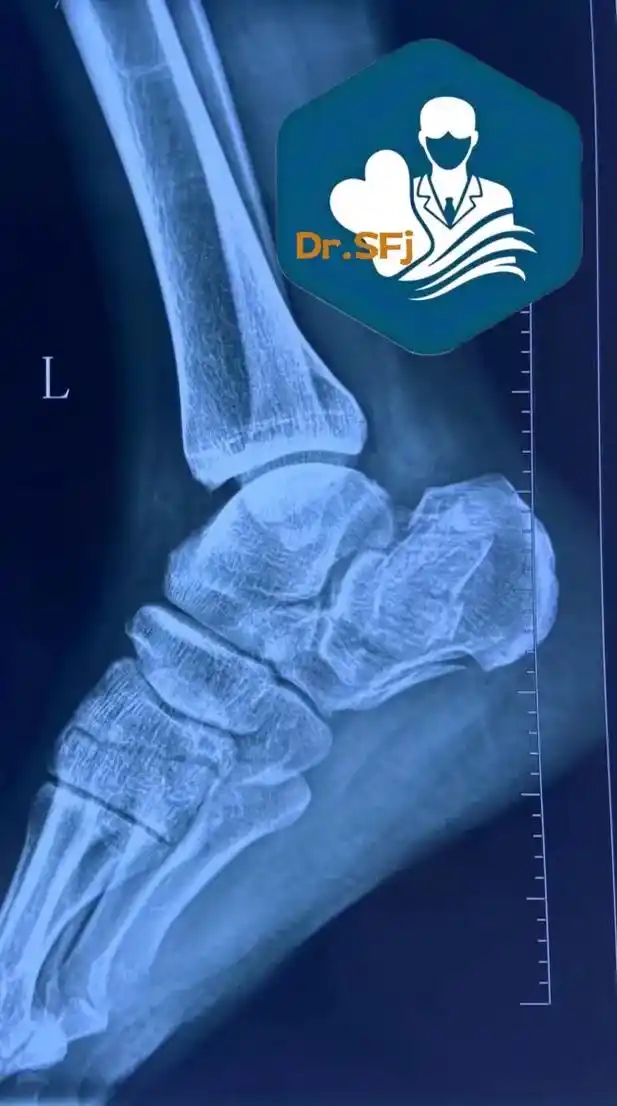

男性51岁,因高处摔伤至双跟骨粉碎性骨折,右跟骨如何复位才能减少功能

后跟骨粉碎性骨折中医保守治疗

近期完成的跟骨粉碎性骨折.#骨折 #跟骨骨折 #跟骨粉碎性骨

"足跟骨粉碎性骨折"住院多久?这名男子10小时即出院!

1.3号跟骨粉碎性手术的折友们,你们都脱拐了吗?#

脚后跟粉碎性骨折后要不要取钢板,主要看用的材料类型和骨头恢复

有人也脚跟骨粉碎性骨折过吗?有没有使用过像我这样的外固定支架?